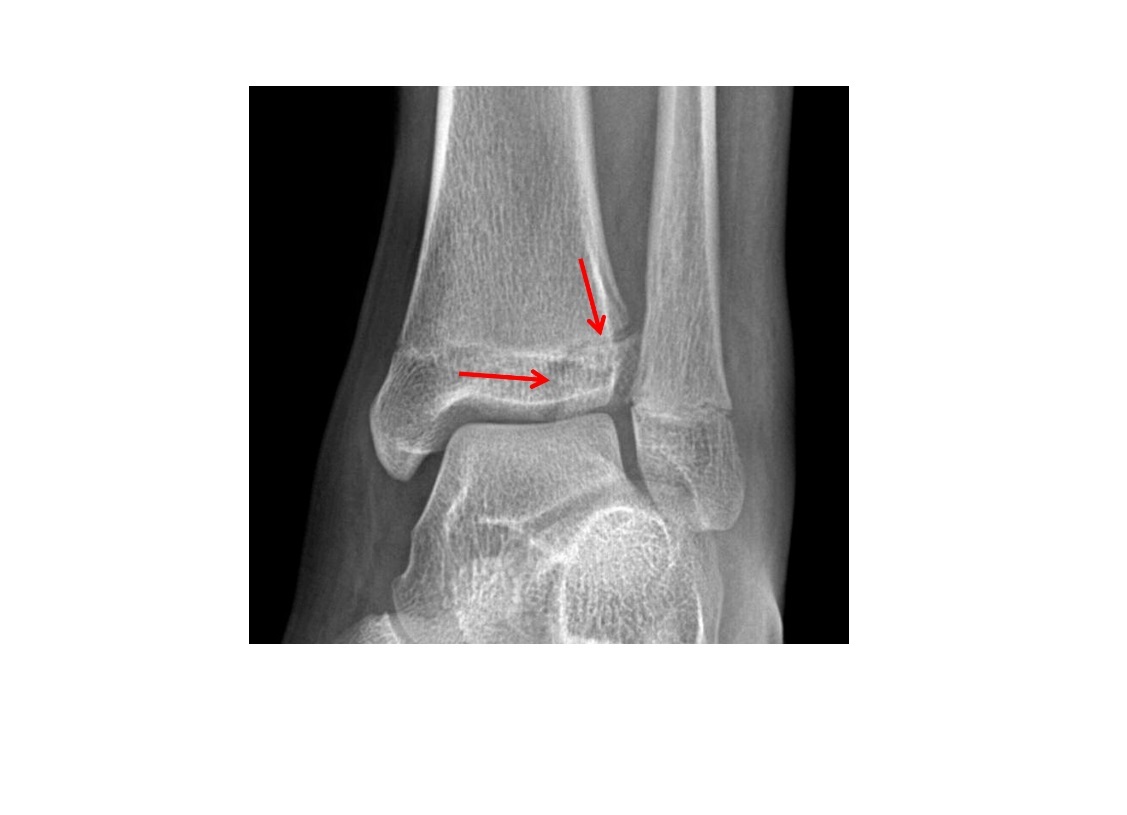

Tillaux fracture

Salter-Harris 3 = through the anterolateral distal tibial epiphysis

Triplane fracture

Salter-harris 4 =Vertical component through the epiphysis , horizontal component through the physis , oblique through metaphysis